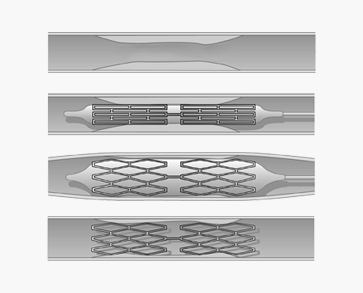

3. 경동맥 풍선 확장술 및 뇌혈관 스텐트 삽입술

<경동맥 풍선 확장술 및 뇌혈관 스텐트 삽입술>

- 신경중재(neurointervention)라는 용어는 다양한 신경계 질환을 두개골이나 척추골 절개 없이 영상 유도(image guidance)하에서 경피적으로 접근하여 치료하는 행위를 말하며, 뇌혈관에서도 동맥경화 등에 의한 협착증이 있을 경우 임상 양상을 고려하여 좁아진 혈관을 넓혀 주기 위해 풍선도관(balloon catheter)을 이용한 혈관성형술을 하거나 필요한 경우 스텐트 삽입술을 실시하고 있습니다.

<경동맥 풍선 확장술 및 뇌혈관 스텐트 삽입술>